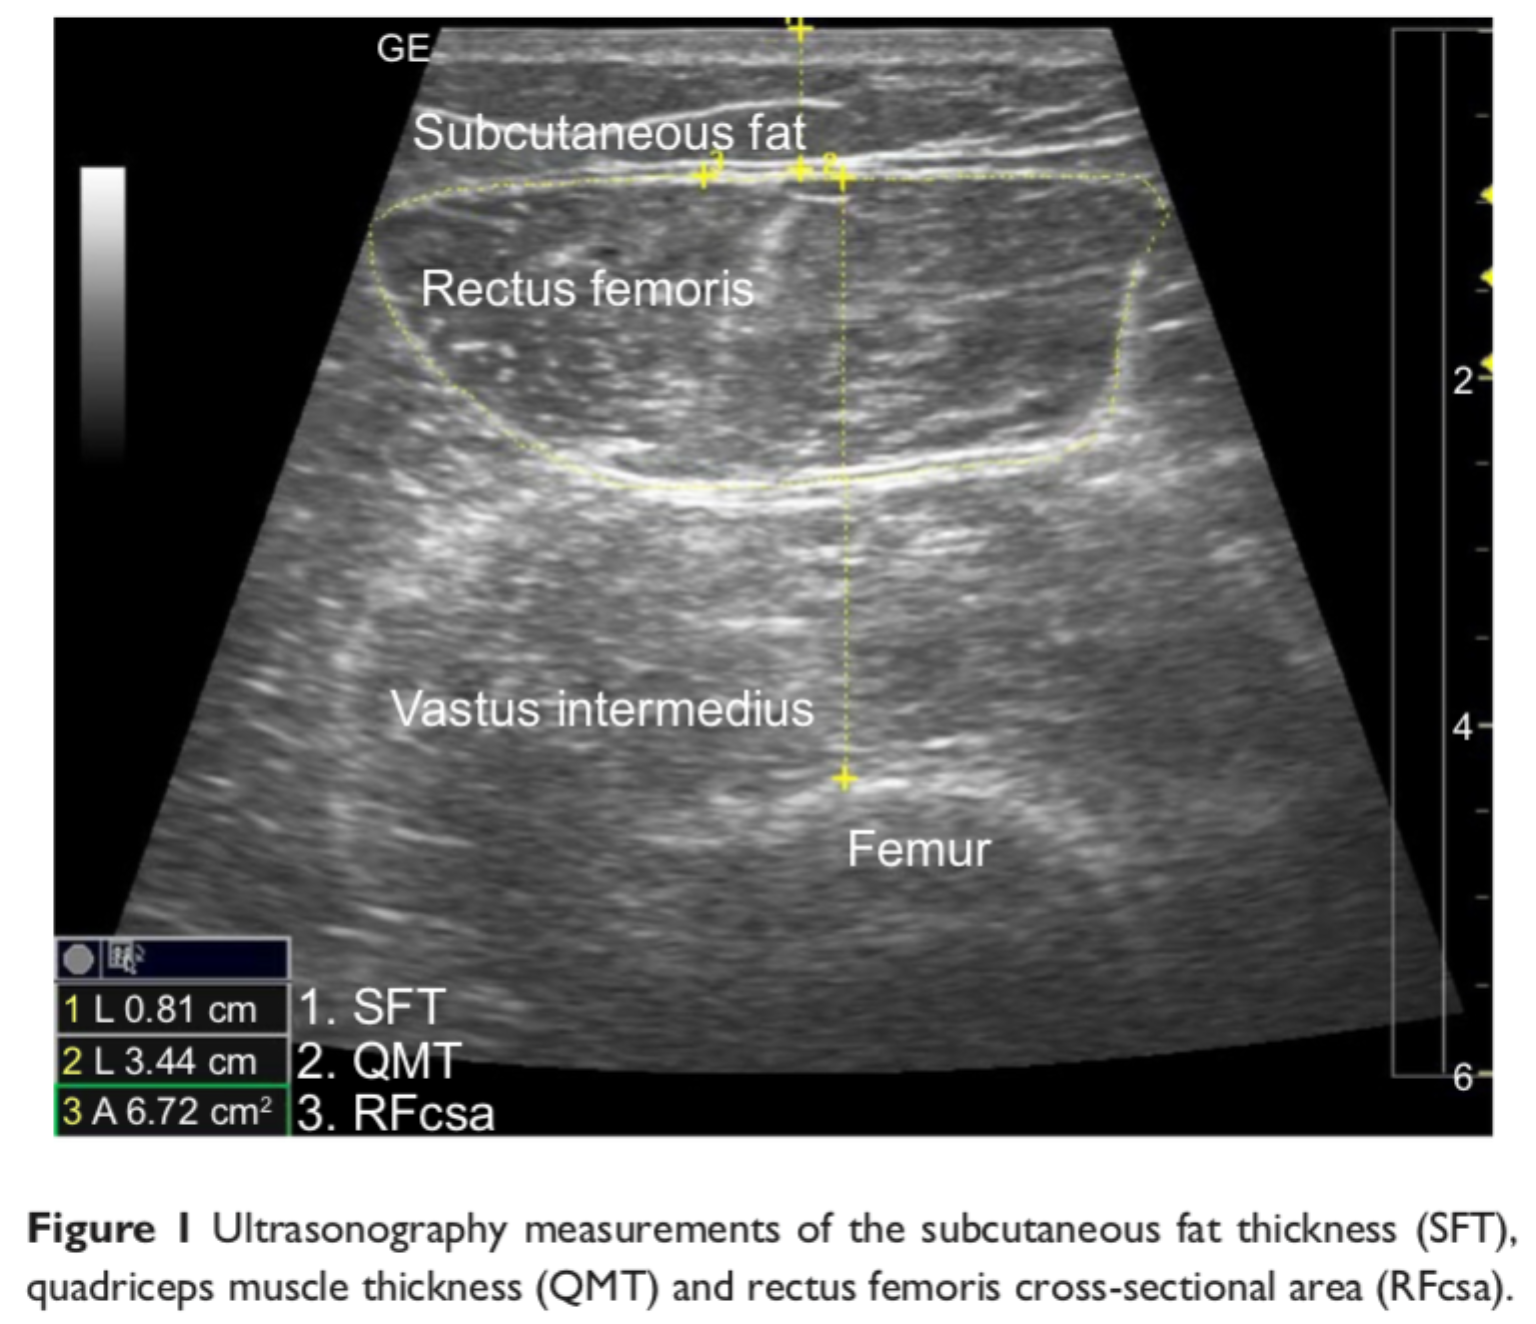

叶熊博士潜心于教学和自然科学研究,不忘初心、默默耕耘。分别主持厅局级和省部级项目各1项,校级项目3项,总资助经费30万元,发表第一作者SCI论文3篇,累计影响因子11.133分。于2017年10月,在《Int J Chron Obstruct Pulmon Dis》杂志(IF:3.355)发表题为“Echo intensity of the rectus femoris in stable COPD patients”的研究论文1篇,该研究探索了一种超声图像回声强度定量方法,用于评估慢性阻塞性肺病患者股四头肌功能,有助于早期诊断慢性阻塞性肺病患者的骨骼肌功能失调;于2021年5月,在《Frontiers in Medicine》杂志(IF:5.091)发表题为“A Novel Normalized Cross-Correlation Speckle-Tracking Ultrasound Algorithm for the Evaluation of Diaphragm Deformation”的研究论文1篇,该研究首次把互相关归一算法用于膈肌超声斑点追踪,为研究膈肌动力学提供了一种创新性的方法。该成果是叶熊老师和清华大学生物工程系罗建文研究员团队合作的阶段性成果